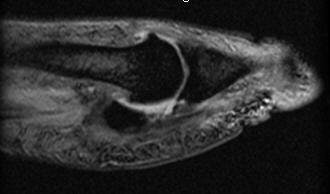

| MR from same player as above. Oblique coronal proton-density-weighted images of the right and left shoulders show the massive bilateral muscle development. |